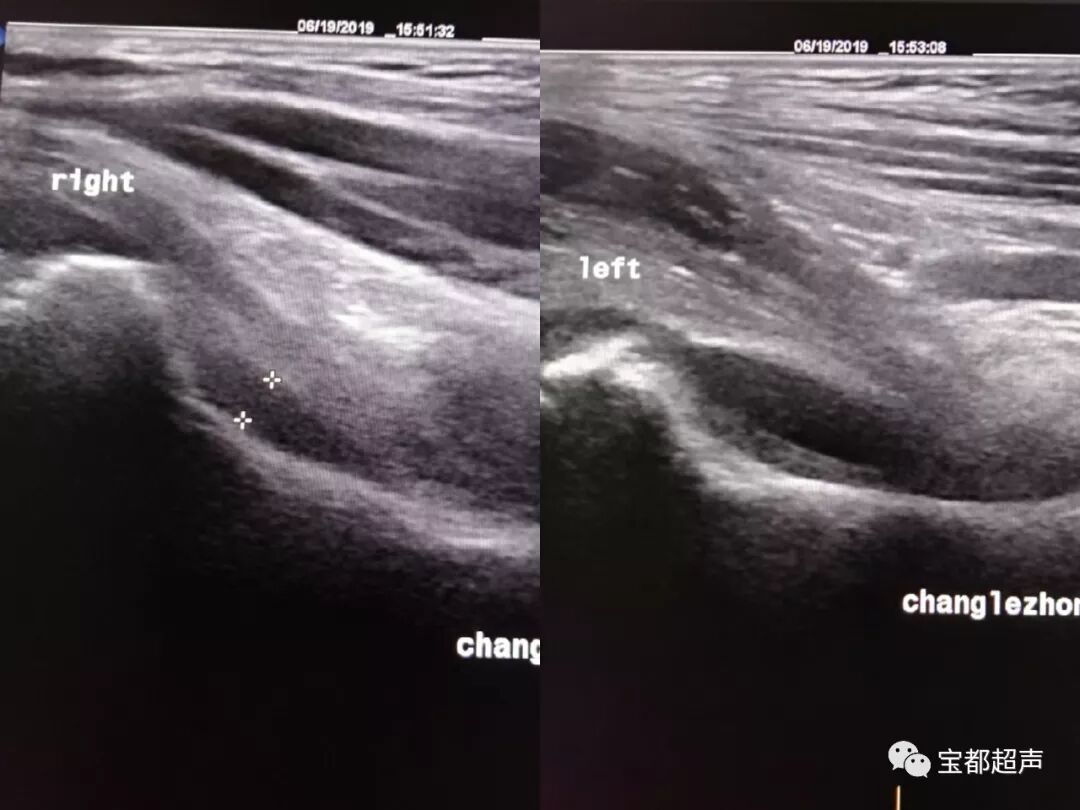

超声表现

一、关节腔积液型:患侧股骨颈颈前间隙较健侧明显增宽大于1mm(儿童2mm有病理意义),关节腔(前隐窝)内有积液,伴或不伴滑膜增厚。

二、关节囊肿胀型:患侧股骨颈颈前间隙较健侧增宽大于1mm,或者整个关节囊厚度大于5-7mm,内回声欠均匀,关节囊与髂腰肌之间的界面凸面向前(正常为凹面向前)。